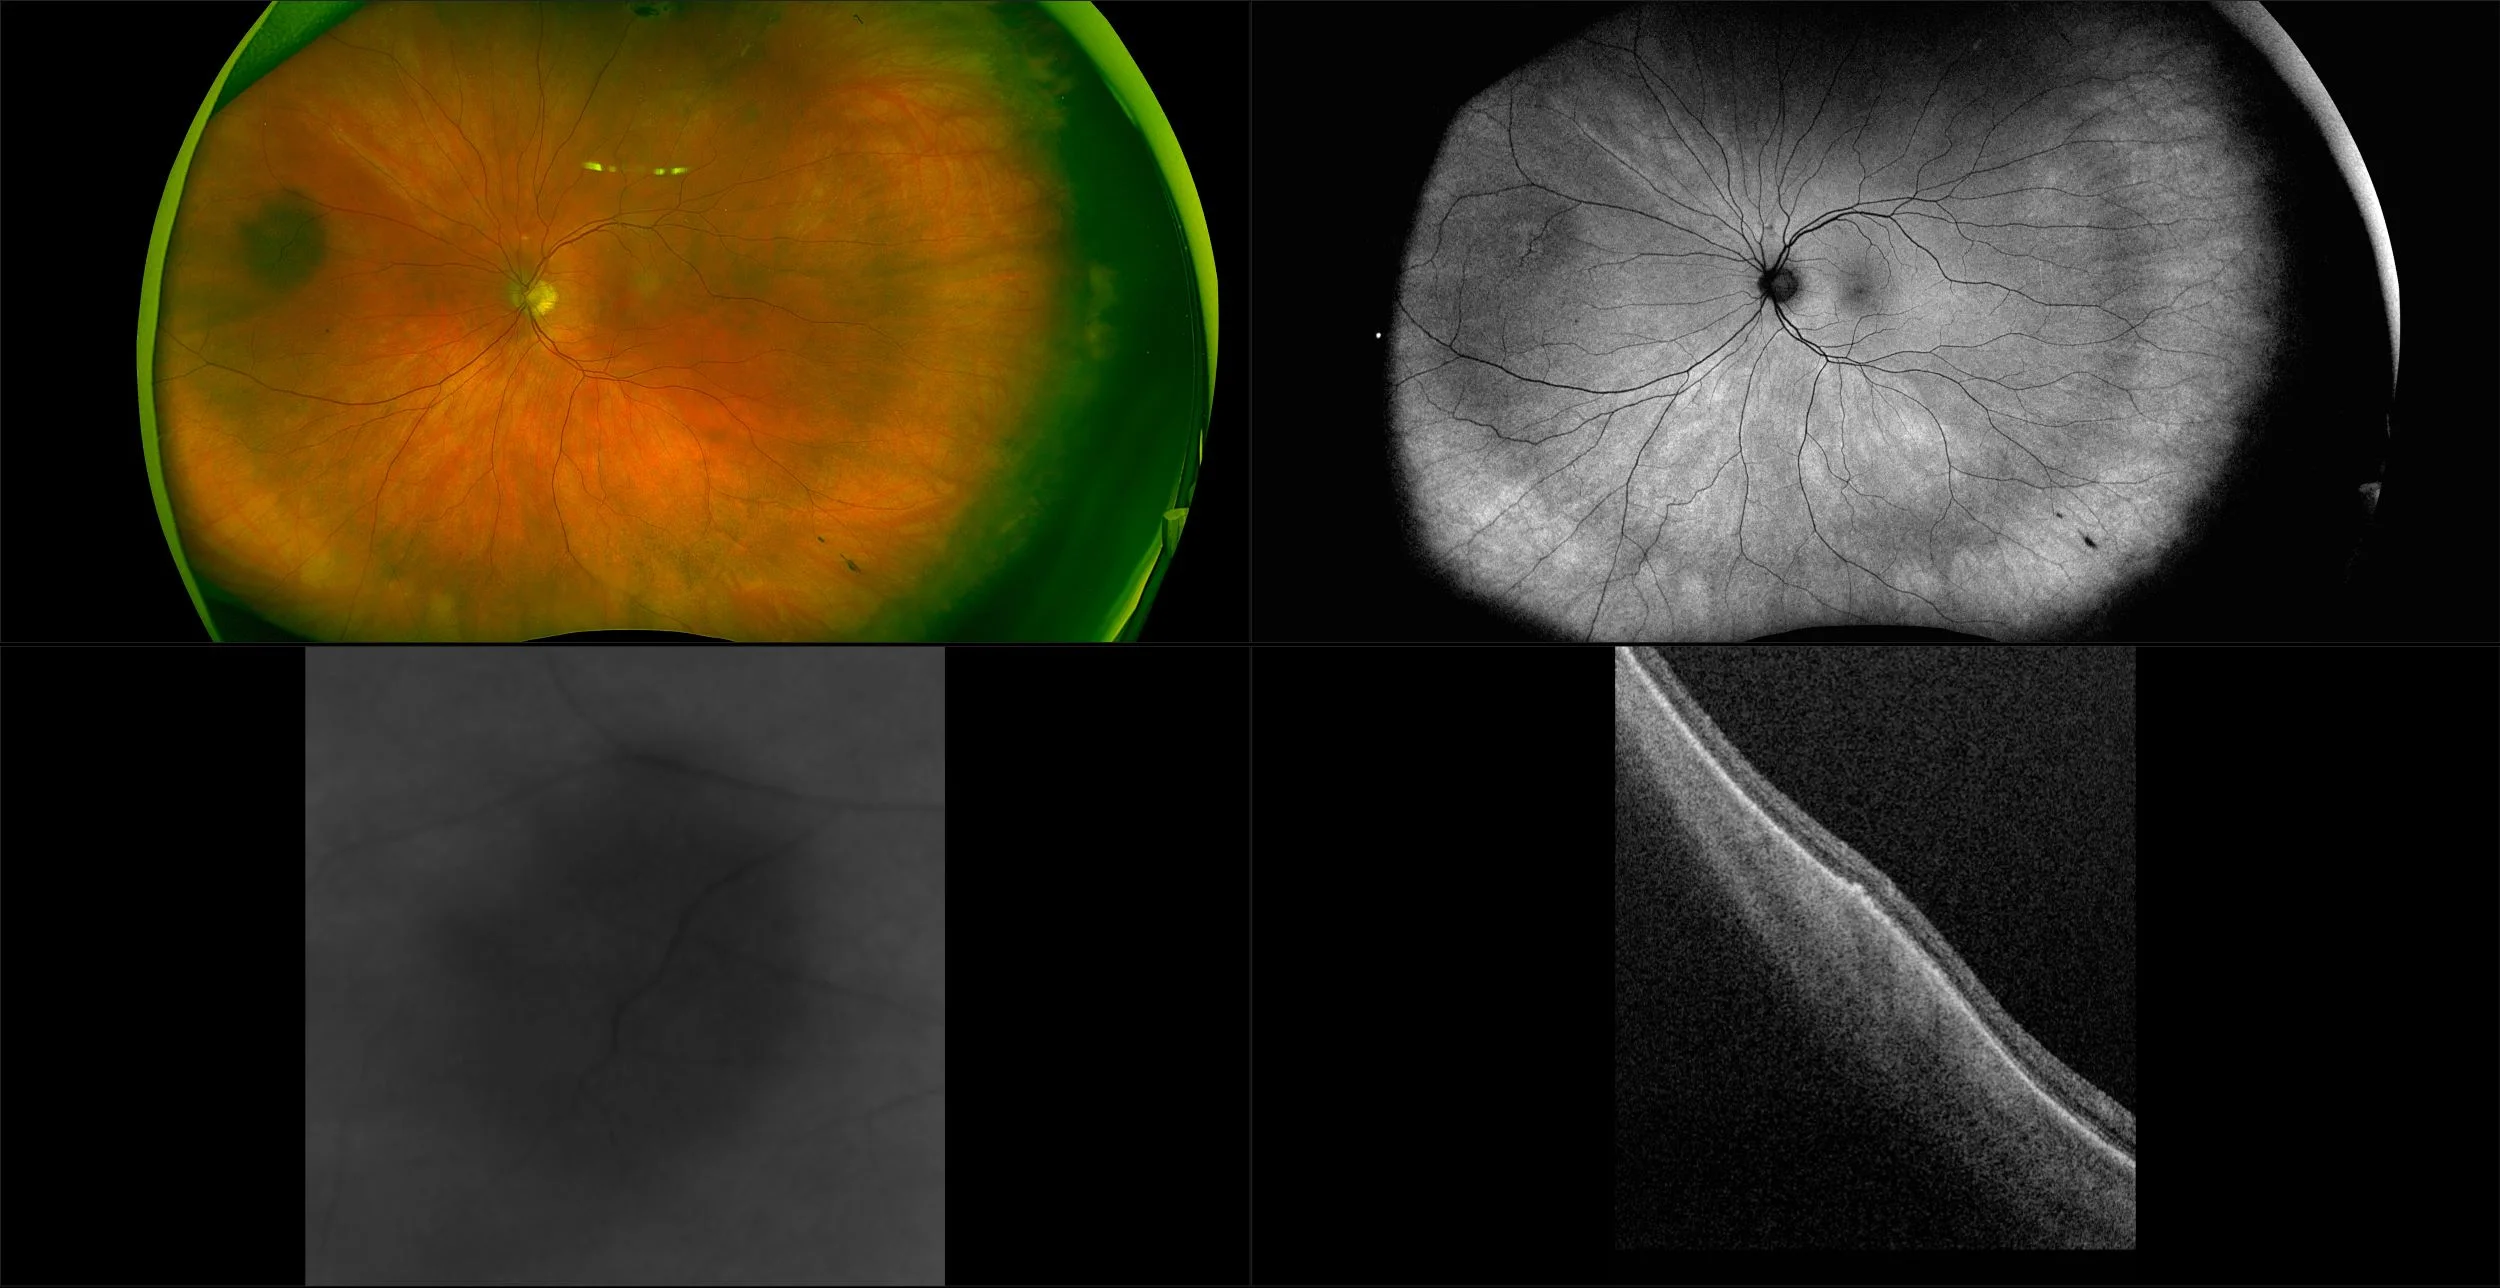

Silverstone - Peripheral Choroidal Nevus, RG, AF, OCT

A choroidal nevus is simply an accumulation of melanocytes in the choroid. They are a space occupying mass or a benign melanoma. Choroidal nevi are slate gray in color, have indistinct margins, and may be slightly elevated (1-2 diopters). Since they are in the choroid, they are usually only seen in the red separation and not the green. The green separation may show the RPE degeneration associated with nevi which is seen as pigment mottling and drusen.